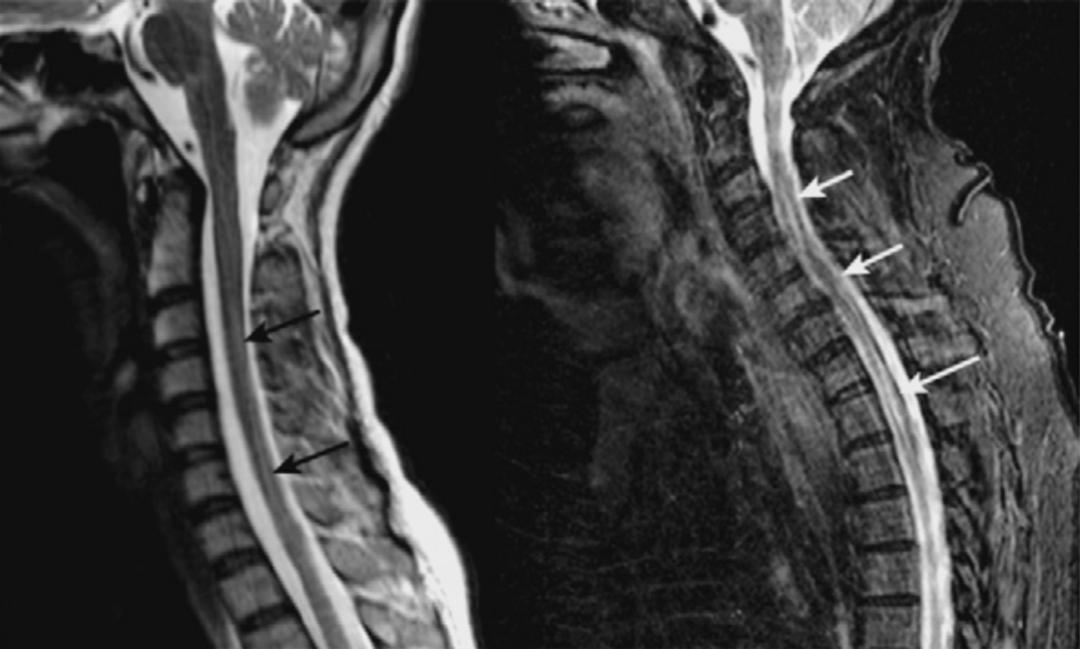

脑脊液流动伪影常易误诊为病变,需与椎管内占位相鉴别。如脊髓背侧脑脊液中可见多个不连续的低信号区,在不同序列成像中表现不同,有时可通过梯度回波 T2 加权像消除此伪影。

截断伪影常见于 MR 信号强度突然变化的组织界面,如脂肪-肌肉和脊髓-脑脊液界面,可能导致脊髓内出现虚假高信号,易被误解为脊髓空洞或损伤。通过校正编码方向等方法可改善。

蓝色箭头所指的是由脊髓腔内脑脊液流动所形成的流动伪影,白色箭头所指的则是截断伪影。蓝色和白色箭头所呈现的征象均属于伪影,椎管和脊髓实际上是正常的,而星号区域为 L1 椎体血管瘤。